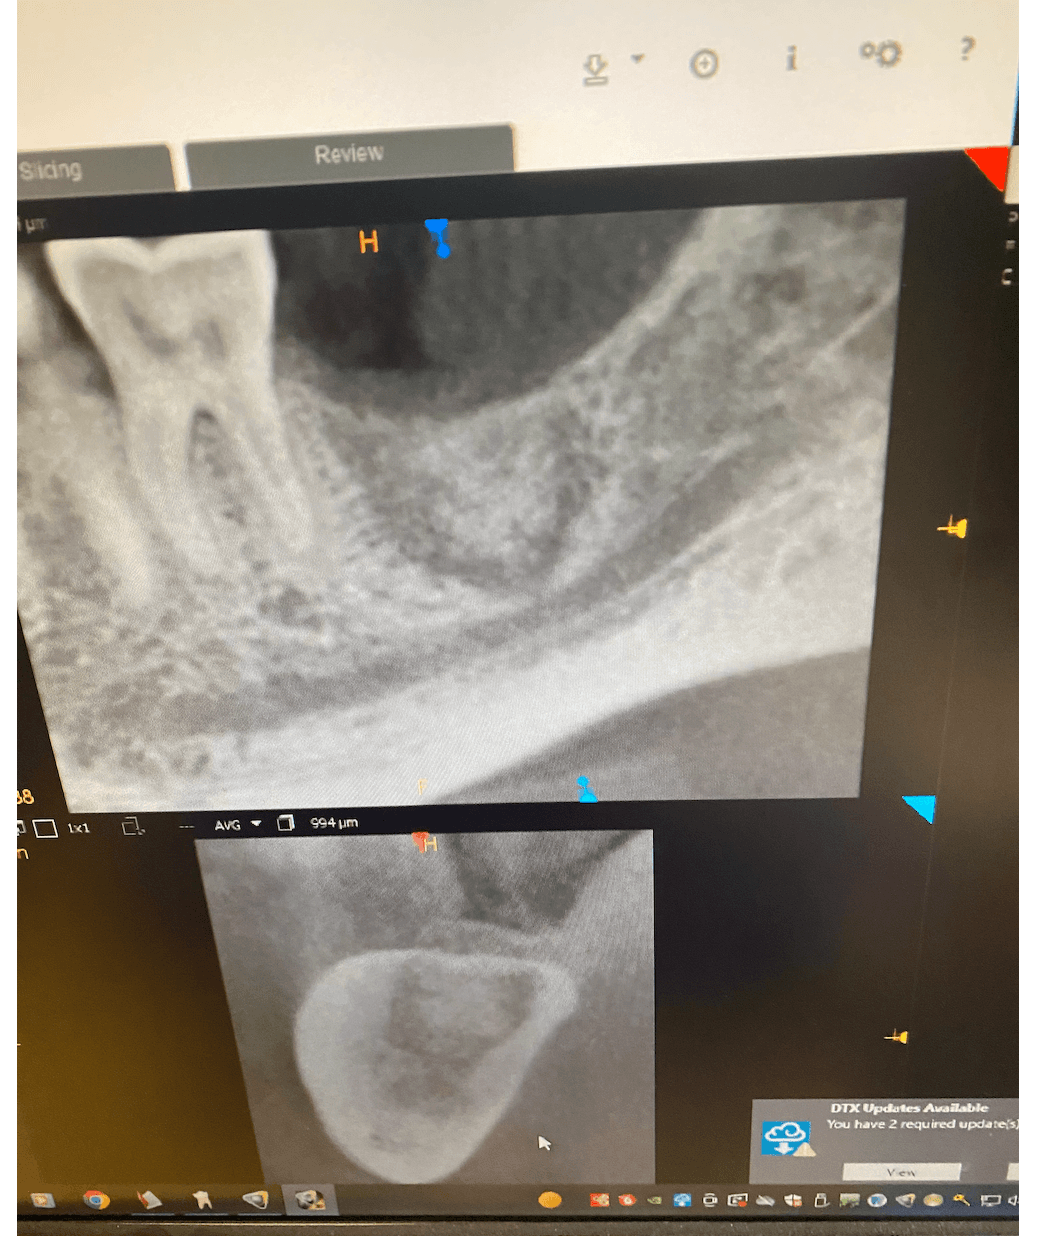

I would appreciate your expertise on this CT scan. I have placed a bone graft in December on #18 and due to the proximity to the IAN canal I did not currette the socket very aggressively.

When the patient returned for follow up it showed fibrous encapsulation around the graft and I was hoping to get advise on how to handle the case.